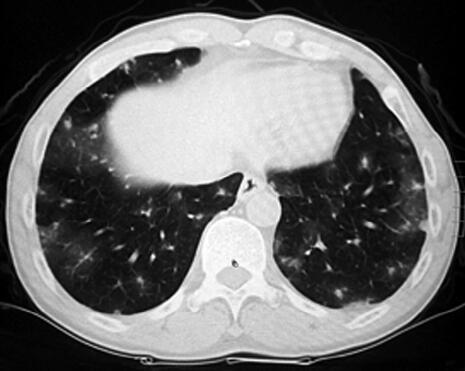

患者为农民,主要从事家务。既往身体健康,无呼吸系统疾病。半年前开始出现少量痰中带血,无明确诱因,其后咯整口鲜血,无胸痛,有轻度活动后气短。于当地诊所检查,胸部CT示双肺多发磨玻璃影,团片影、边缘呈晕轮征(图1)。给予抗感染及止血对症治疗(具体不详),咯血有所减轻。两个月前,患者为明确诊断就诊于我院,进行免疫生化检测时发现P-ANCA(±),诊断为弥漫性肺泡出血,肺血管炎可能性大,止血治疗的同时给予甲泼尼龙治疗,咯血症状消失,气短有所缓解,复查胸部CT:晕轮征及磨玻璃影有所吸收(2)。继续甲泼尼龙24mg,每日1次,院外口服治疗。患者应用甲泼尼龙1个月后减量至每日20mg,但此后应用不规范,剂量波动于每日16~20mg。患者于入院前半个月再次出现痰中带血,伴胸闷气短,咯血量有增加趋势。

图1

通过问诊可明确,患者既往无呼吸系统疾病,本次发病无明显诱因出现咯血,胸部影像学提示肺部有多发磨玻璃影及晕轮征。曾被诊断为肺血管炎,并应用糖皮质激素治疗,治疗之初有一定改善,咯血症状消失,但激素减量过程中咯血症状复发。结合患者既往诊断和治疗过程,肺血管炎诊断似乎成立,咯血复发的原因可能是激素减量及使用不规律。

本例患者病初磨玻璃影和晕轮征,结合咯血病史,考虑可能的诊断为血管炎是正确的。同时需要注意晕轮征缺乏特异性,但对缩小鉴别诊断范围有一定的帮助。另外,影像学需要动态评估,第一次就诊,在激素治疗后晕轮征有所吸收,而结节影没有吸收,应引起足够的重视去鉴别恶性疾病,引起晕轮征的常见恶性疾病包括:细支气管肺泡癌,肺鳞癌,肺腺癌,血管肉瘤,骨肉瘤,Kaposi肉瘤等。在诊断不确切时,如果病情允许,应积极进行组织病理学检查。